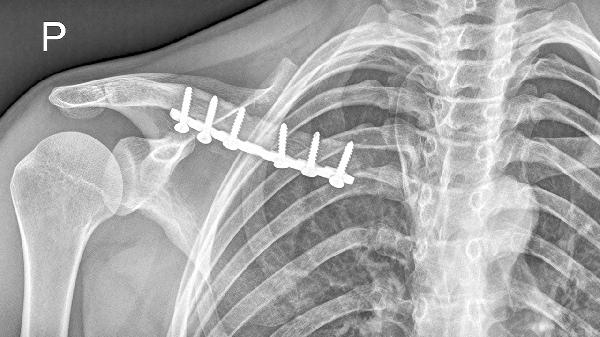

4、锁骨外侧端异常隆起或凹陷

完全性骨折时,由于肌肉牵拉作用,锁骨外侧端可能出现明显移位,表现为局部隆起或凹陷。通过肉眼观察和触诊可发现锁骨轮廓异常,这是诊断的重要依据之一。不完全骨折或韧带损伤时,这种畸形可能不明显。